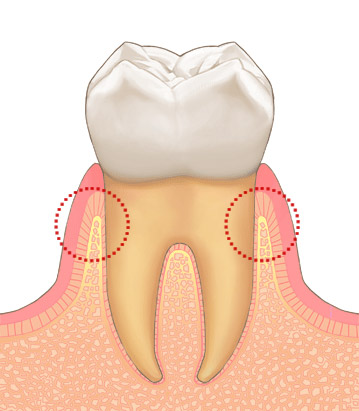

歯肉が炎症を起こし、歯槽骨の吸収を起こし始めます。

ここまで歯周病が進行するとGTR法が必要になります。

かなり歯槽骨の吸収がすすみ、歯の動きが感じられる様になり、膿がでて口臭が強くなります。